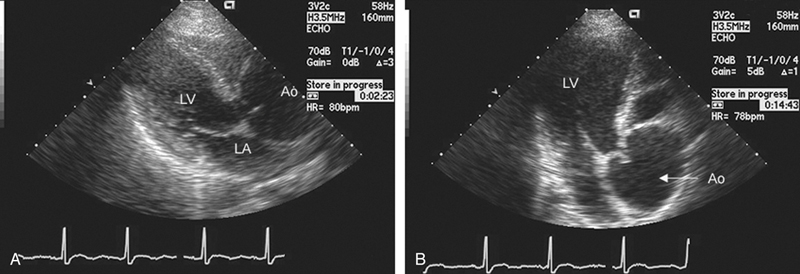

فحوصات تشخيصية لبعض امراض القلب والشرايين التاجية